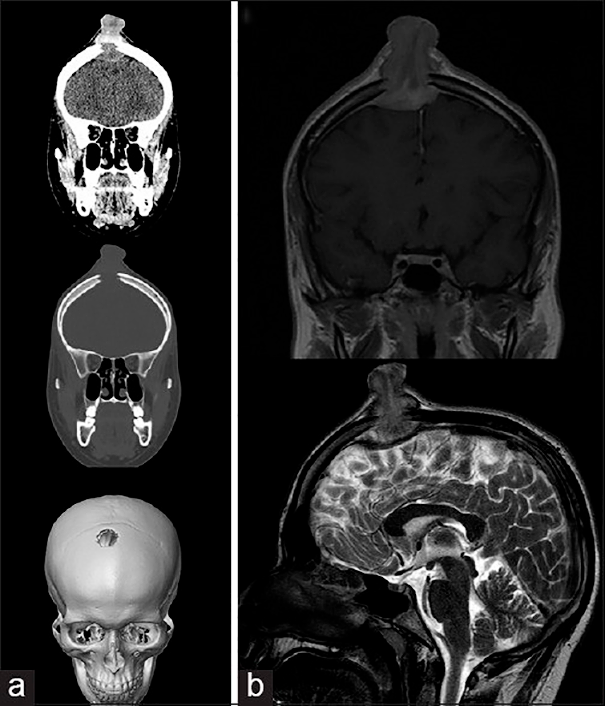

Молодой человек 17 лет был госпитализирован по поводу увеличивающегося в течение последних 6 недель образования волосистой части головы. Образование при пальпации болезненно, из‑за изъязвления периодически кровоточит, однако неврологического дефицита не выявлено. При КТ и МРТ выявлен крупный очаг в лобной кости справа, сдавливающий верхний сагиттальный синус. Проведена тотальная резекция образования, подтвержден диагноз «лангергансоклеточный гистиоцитоз кости черепа». На амбулаторном этапе проводилась терапия цитостатиком.

Рисунок 6. (а) КТ-исследование без контрастирования — фронтальное сканирование (верхняя и средняя часть) и 3D-реконструкция черепа (нижняя часть). (b) МРТ-сканирование. Т1‑взвешенное изображение во фронтальной плоскости (сверху) и Т2‑взвешенное изображение в сагиттальной плоскости